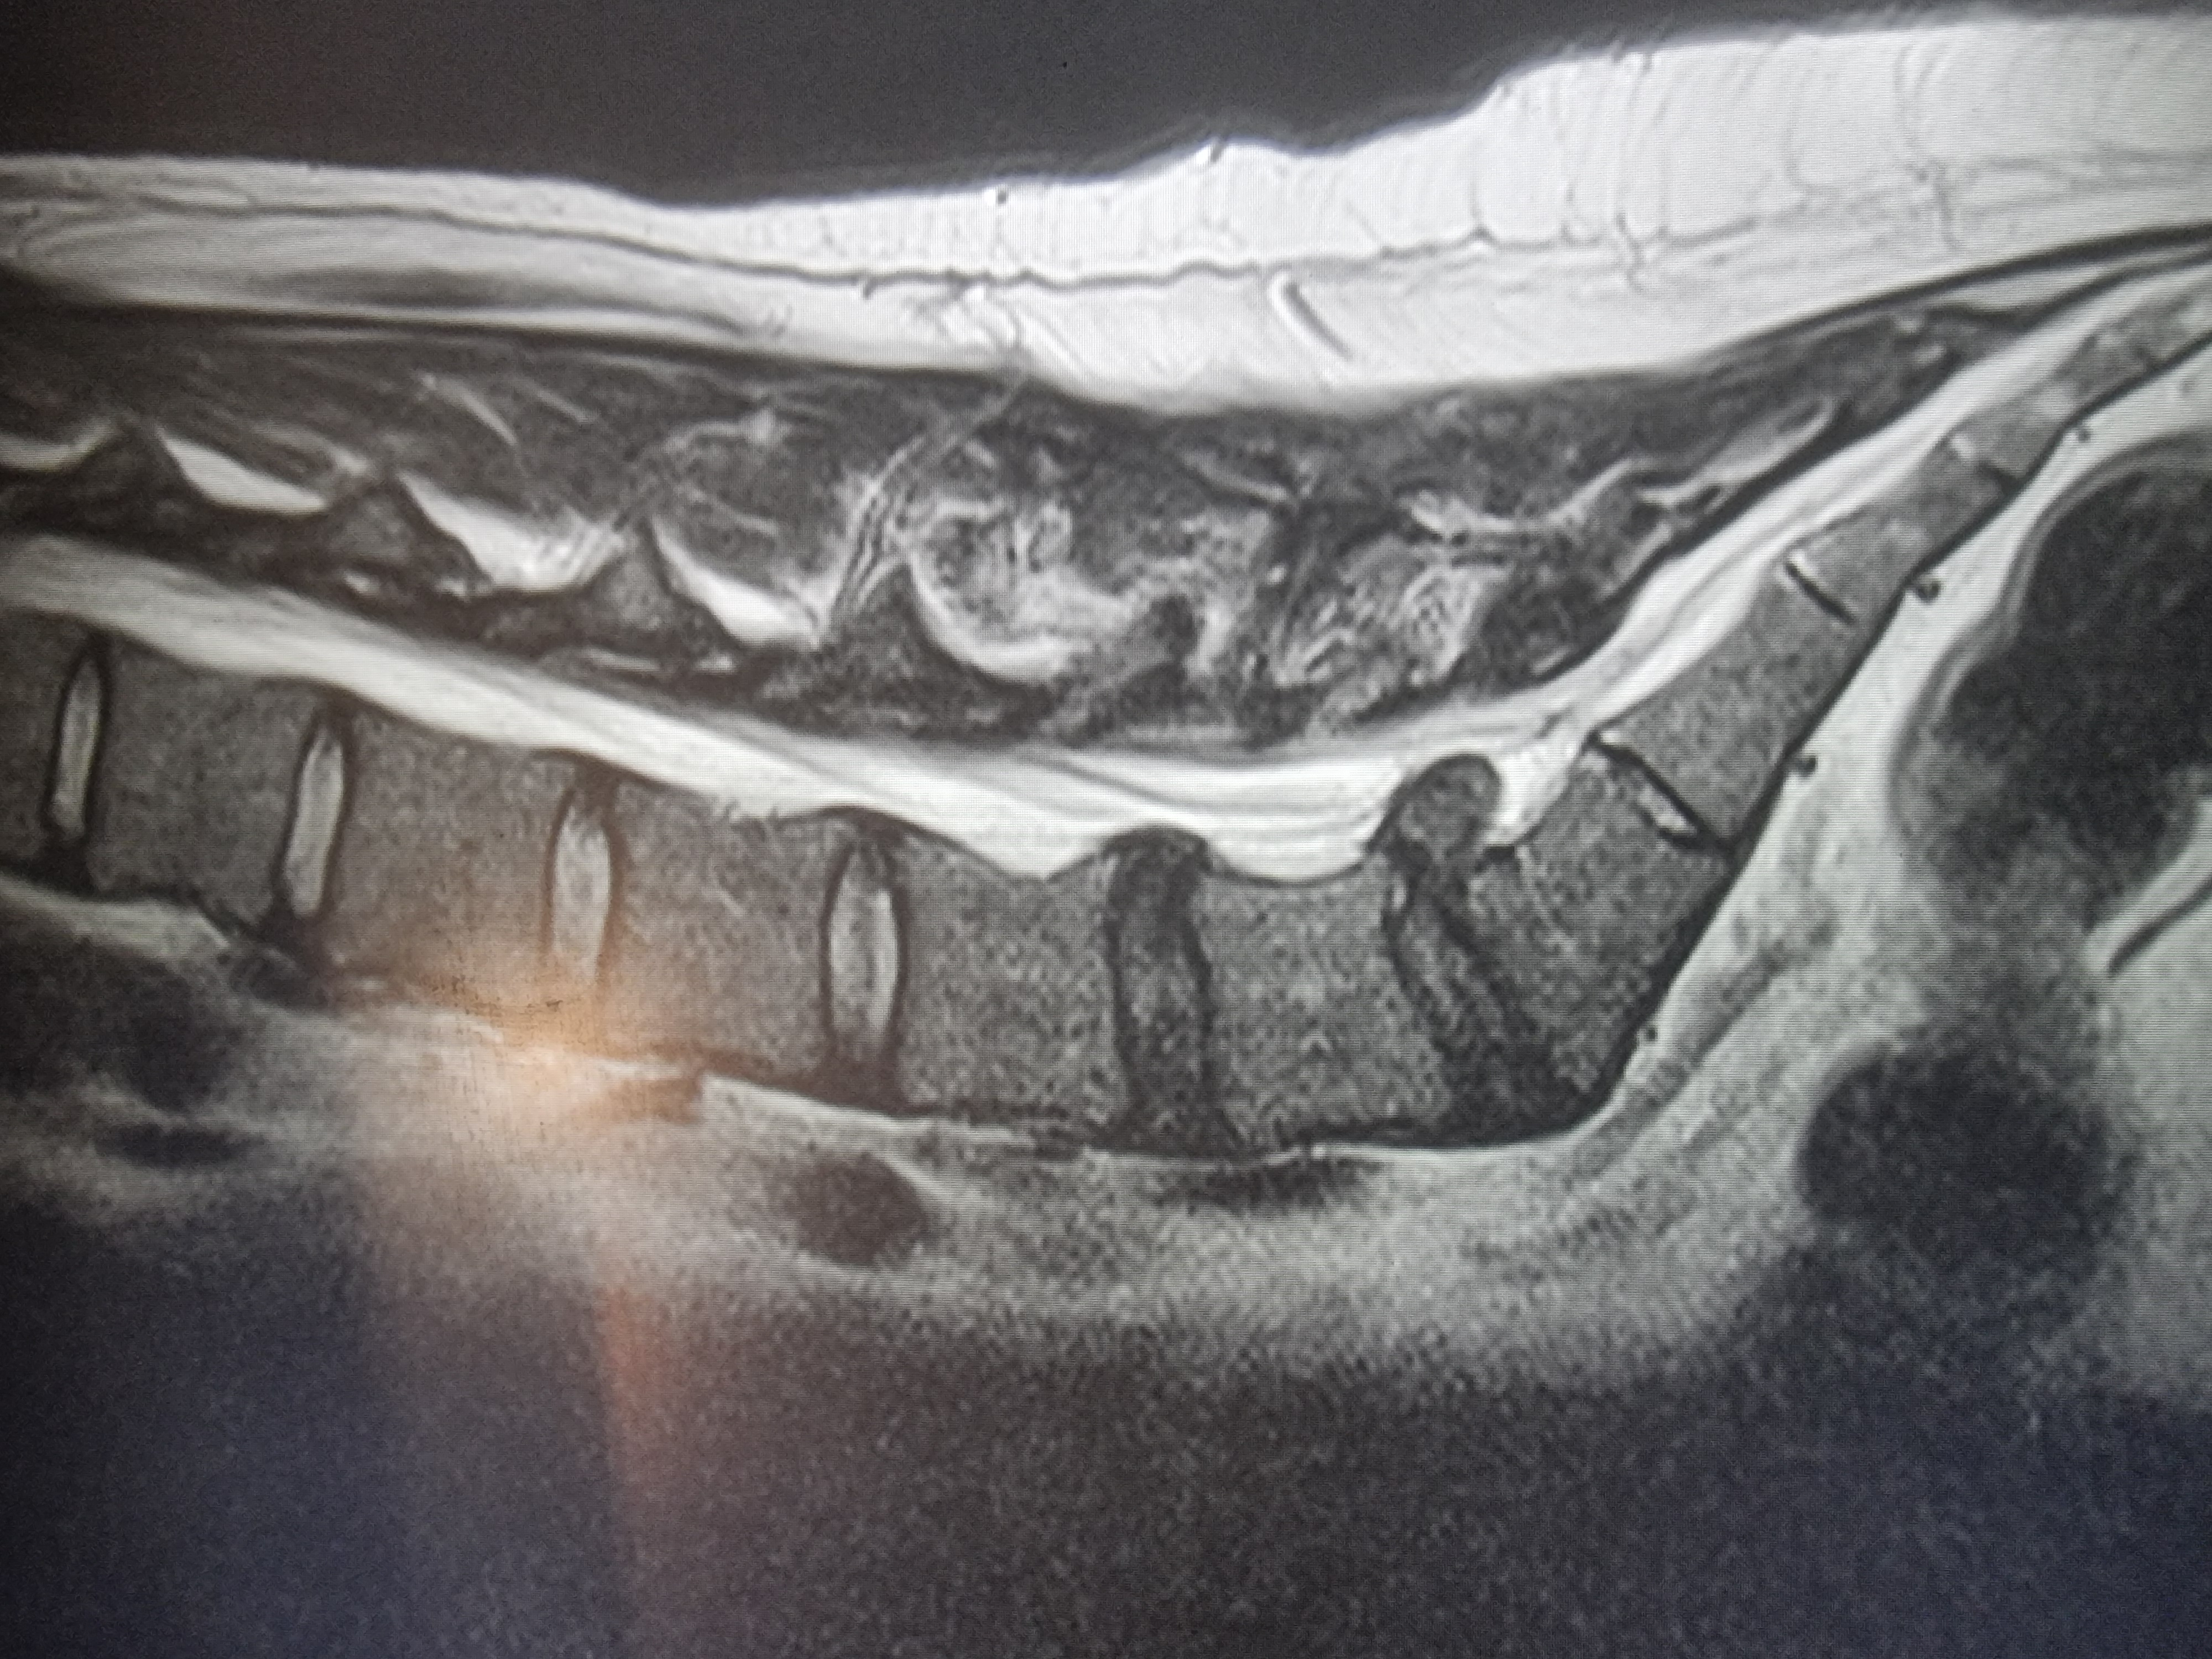

Грыжа 12 мм. - Дайте рекомендации, пожалуйста. Аноним 25/10/25 Суб 19:03:35 1646369 1

На этой неделе сделал МРТ и... грыжа 12 мм. с разрывом (см. 1 фото). о_О

У тебя экструзия на L5-S1, протрузия L4-L5.